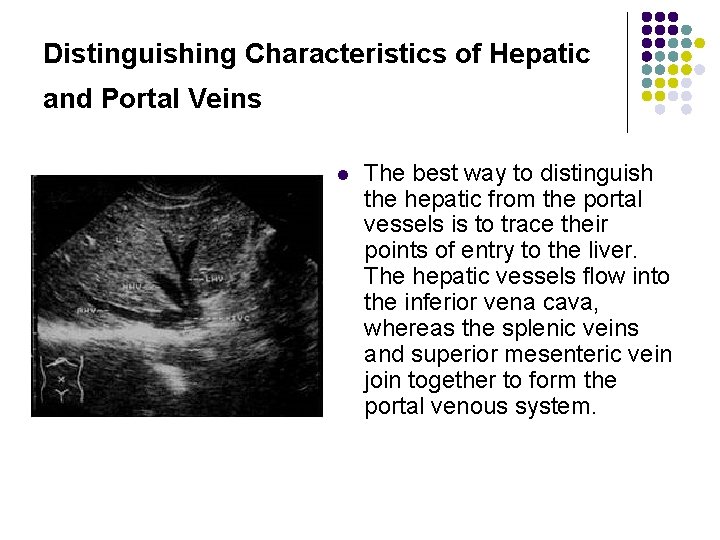

Distinguishing Characteristics of Hepatic and Portal Veins l The best way to distinguish the hepatic from the portal vessels is to trace their points of entry to the liver. The hepatic vessels flow into the inferior vena cava, whereas the splenic veins and superior mesenteric vein join together to form the portal venous system.